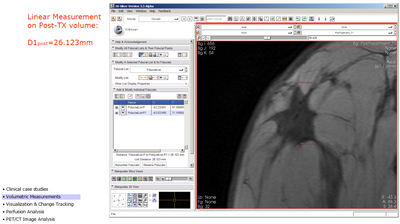

Linear Measurement (from draft slides)

measuring pre-TX tumor with fiducials, orthogonal dimension

• Linear Measurements:

• scroll to slice with largest diameter Dmax

• measure Dmax and orthogonal Dmax on both treatment timepoints using the linear measurement widget.